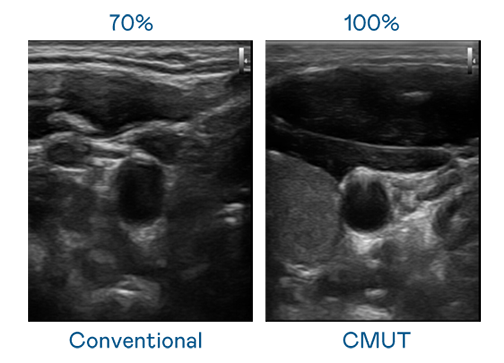

CMUT 技术是一种用电容式微机电元件来产生超音波讯号的技术。与传统 PZT 压电式技术相比,CMUT 频宽增加 30%,更宽频的超音波讯号让影像解析度大幅提升,是实现高影像品质医疗超音波扫描、促进精准医疗发展的关键技术。

超音波影像的解析度高低,首先取决于探头能发出的讯号频宽。爱游戏官网 CMUT 可提供高清晰的超音波讯号,提供高频宽、高灵敏度、影像纹理细节更高的超音波影像,协助医护人员缩短影像判读时间及利用精准的医疗影像进行诊断。